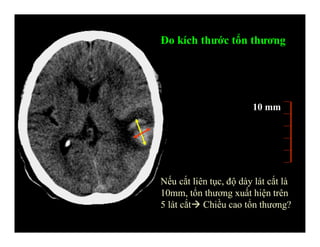

Độ dày lát cắt

Khoảng cách lát cắt

a b

Đo kích thước tổn thương

10 mm

Nếu cắt liên tục, độ dày lát cắt là

10mm, tổn thương xuất hiện trên

5 lát cắt Chiều cao tổn thương?